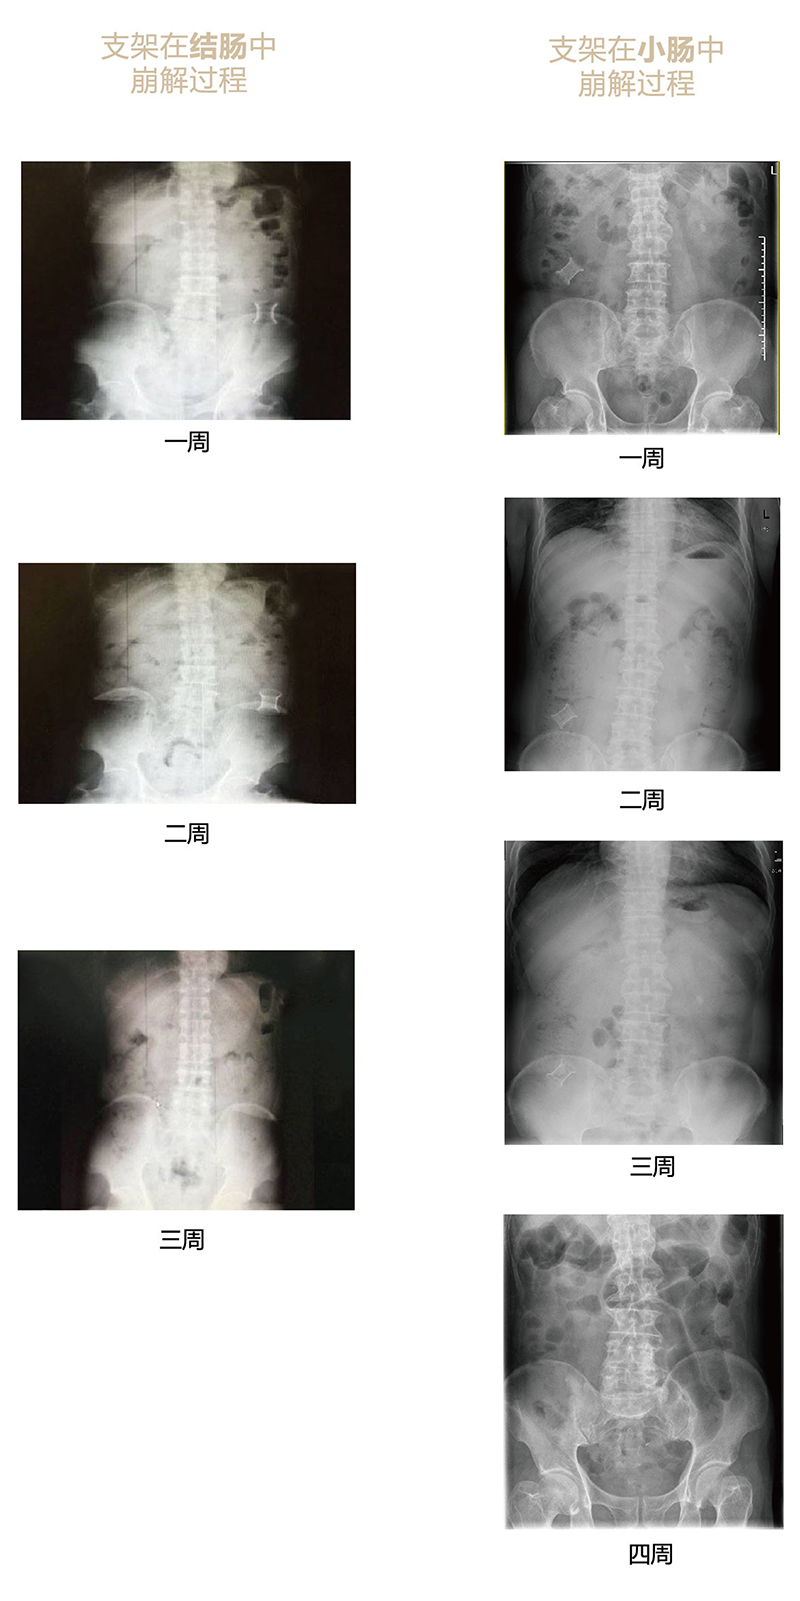

可崩解腸道吻合器由聚乙醇酸(PGA)與硫酸鋇按重量比7:1混合注塑制成,在X線下顯影,可動(dòng)態(tài)追蹤可崩解腸道吻合器(支架)在腸道內(nèi)崩解過(guò)程。

為解決該問(wèn)題,蔡秀軍教授在“支架法空腔臟器吻合技術(shù)”的理念基礎(chǔ)上,又發(fā)明了“蔡氏腸轉(zhuǎn)流術(shù)”,這是一種應(yīng)用可崩解腸道吻合器HB型(可崩解腸轉(zhuǎn)流支架)(發(fā)明專利號(hào):201910794214.3),的支架法腸道轉(zhuǎn)流術(shù),此創(chuàng)新術(shù)式既能保護(hù)低位吻合口,更避免了回納術(shù)??杀澜饽c轉(zhuǎn)流支架在直腸癌根治術(shù)中植入遠(yuǎn)端回腸,可確保完全阻斷腸腔,用腸造瘺管在轉(zhuǎn)流支架近端行腸造瘺,起到完全轉(zhuǎn)流的作用。腸轉(zhuǎn)流支架在二至三周內(nèi)逐漸崩解,并在四周內(nèi)完全排出體外,恢復(fù)腸道通暢后拔除造瘺管,避免了傳統(tǒng)造口回納的二次手術(shù)。該創(chuàng)新術(shù)式具有方法簡(jiǎn)單、吻合時(shí)間短、人體內(nèi)無(wú)異物永久殘留、不破壞吻合口粘膜下血管,并能預(yù)防吻合口漏、可避免人工肛門留置及二次手術(shù)、治療周期可縮短至二至四周、患者生理心理創(chuàng)傷顯著減少。